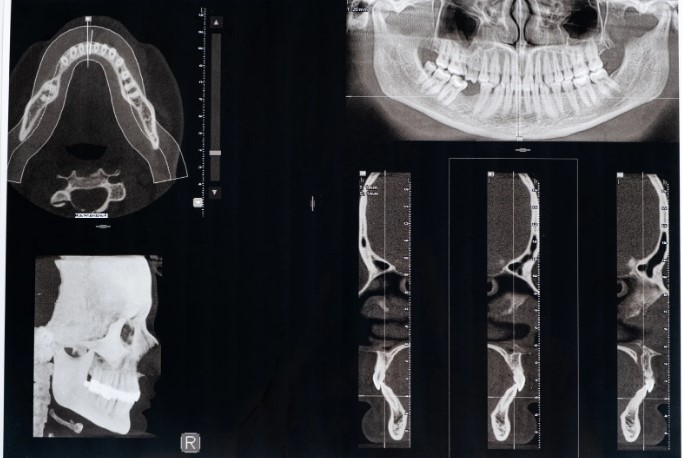

Разобраться, как диагностировать дисфункцию височно-нижнечелюстного сустава, можно с помощью специалиста. Во время осмотра гнатологи и стоматологи обычно используют:

- физикальный осмотр;

- рентгенографию;

- КТ / МРТ;

- электромиографию;

- анализ прикуса;

- функциональную диагностику.

Комплексно они помогают узнать, как проводить лечение дисфункции височно-нижнечелюстного сустава. Первым проводят визуальный физический осмотр для выявления нарушений строения зубов и челюстей. Рентгенография дает возможность оценить состояние костей и суставов челюсти. Найти поврежденные мягкие ткани можно с помощью КТ и МРТ. Проверку работы мышц челюстного сустава совершает электромиография.

Что такое ДВНЧС и причины этого явления, показывает функциональная диагностика с цифровыми сканерами. Они быстро фиксируют нарушения в движении ротовой области. В сложных случаях стоматологи используют все виды диагностики для определения точного диагноза. Но помните, чем раньше вы обратитесь к врачу, тем проще будет проходить диагностика и лечение.